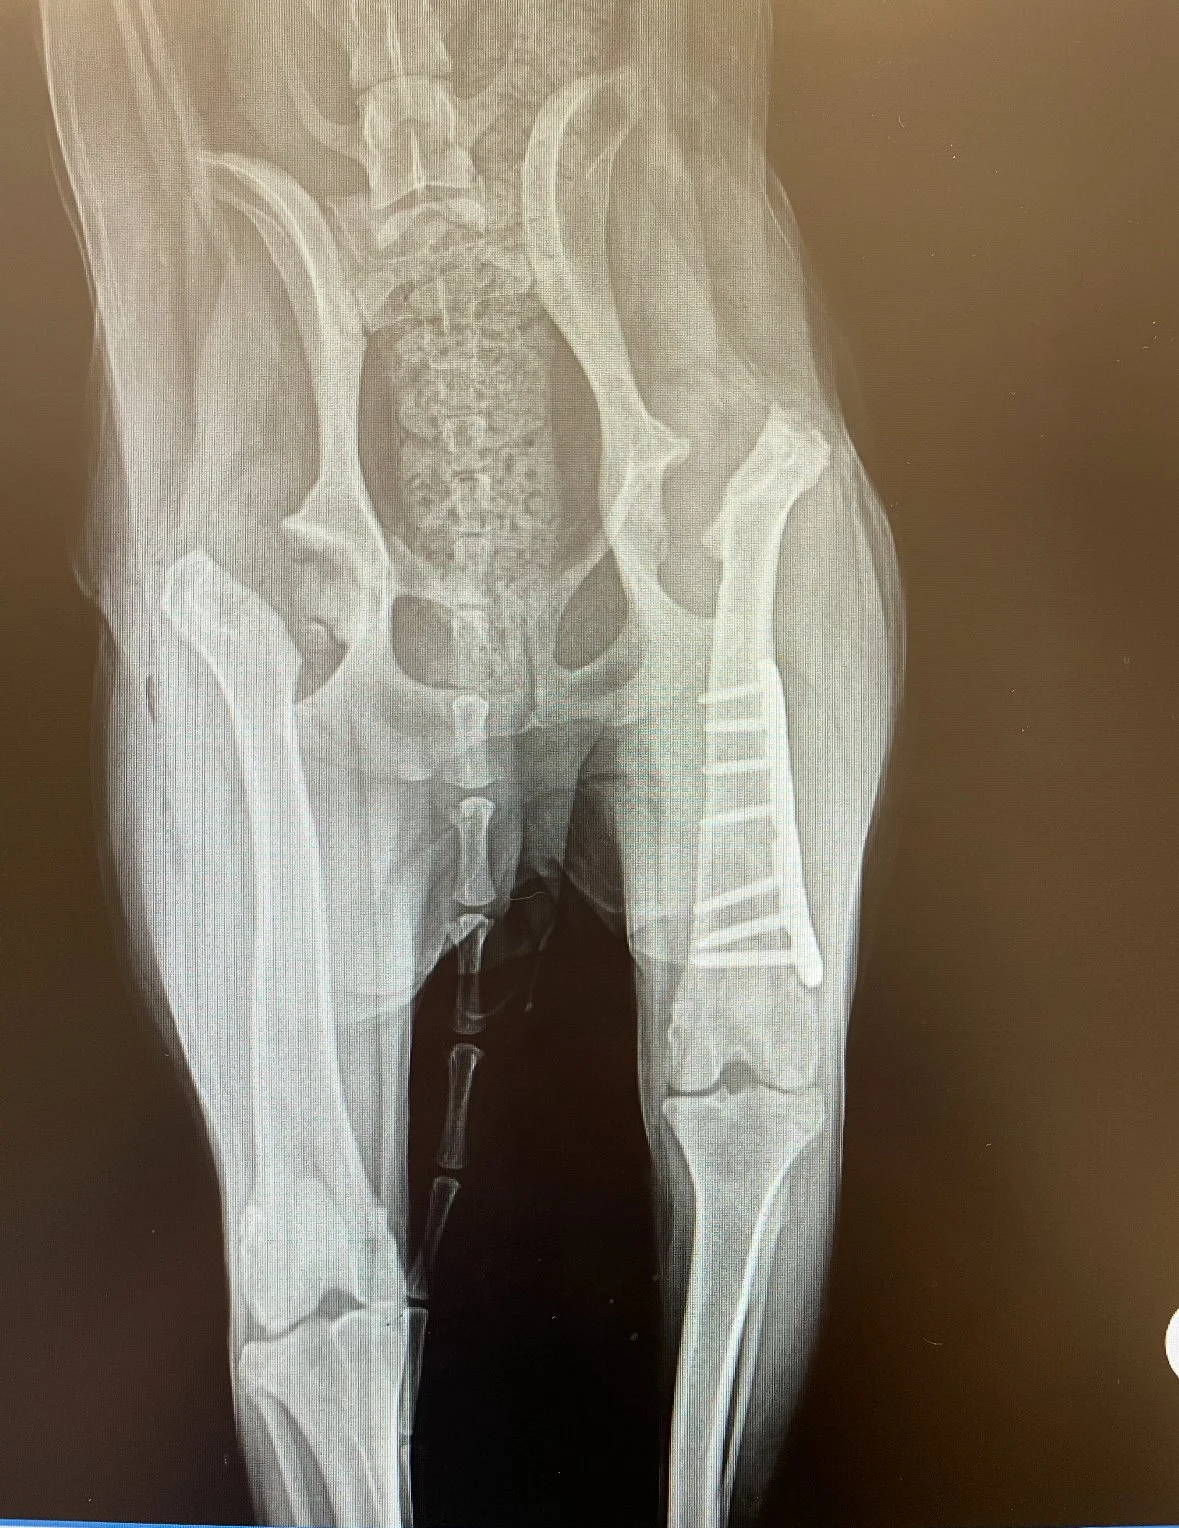

Cali came to NEOCR in May 2025 at just 9 months old. Poor breeding left her with severe hip dysplasia, and she needed major surgery on both hips—care her owner could not afford. Surrendering Cali to NEOCR was a difficult but loving choice that gave her the chance at a healthy future.

After multiple evaluations, NEOCR sent Cali to Purdue University for treatment, where a board member in Indiana fostered her through recovery. Her first hip replacement in July 2025 was complex and unfortunately failed, requiring a corrective FHO surgery and a six‑month recovery. On January 8, 2026, she underwent a second successful FHO on her right hip. She is now healing well and expected to be fully recovered within 6–12 weeks.